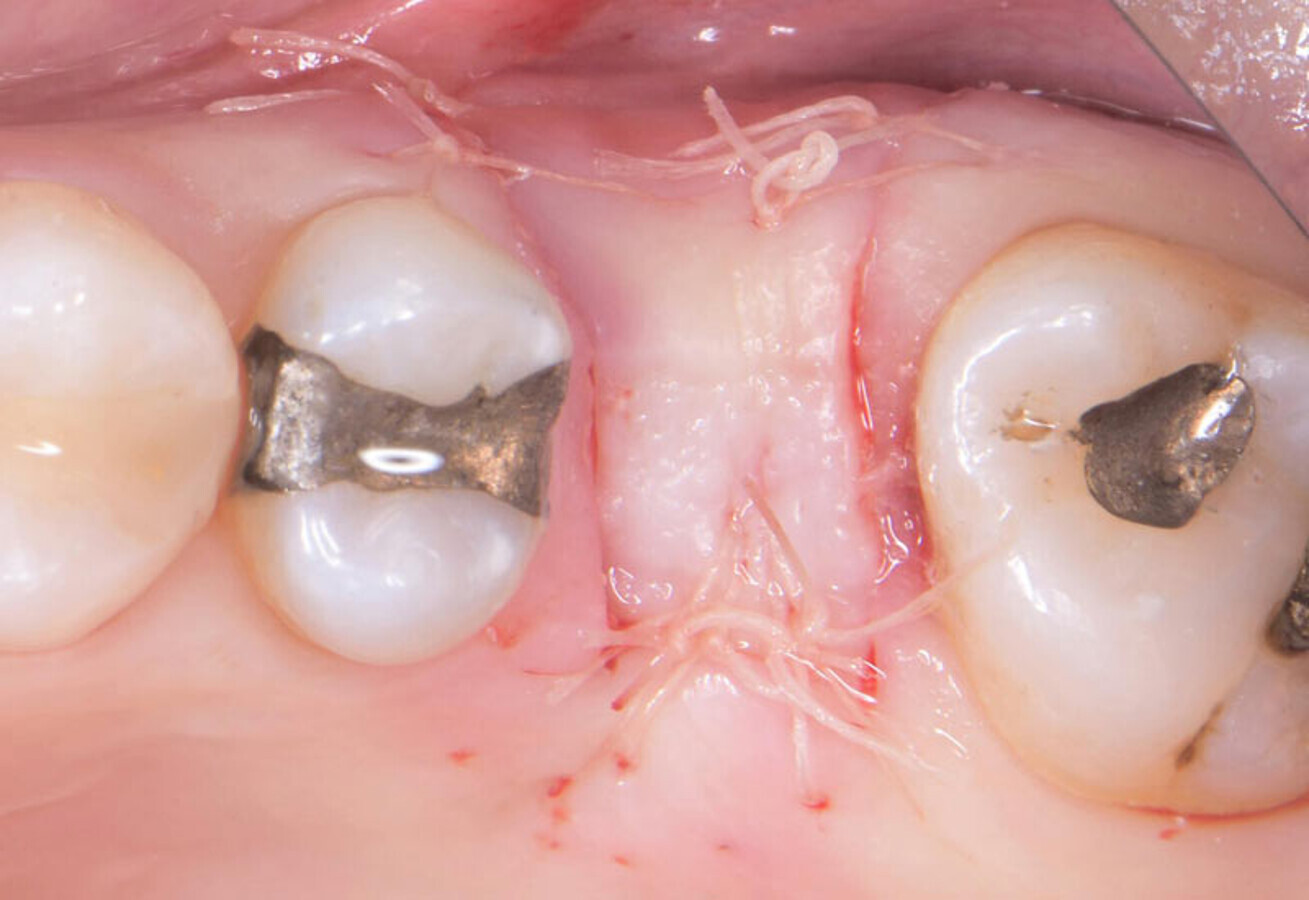

Initial clinical view. Ten months post-extraction.

Sutured with Vicryl 5-0.